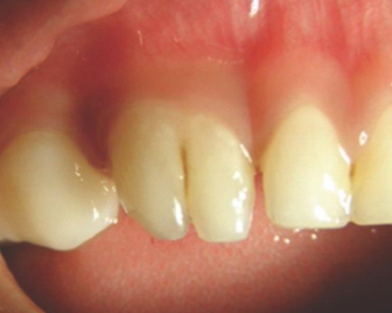

What is calcific metamorphosis?

Response to trauma- canal space fills with hard tissue- narrow calcified- yellow discolouration